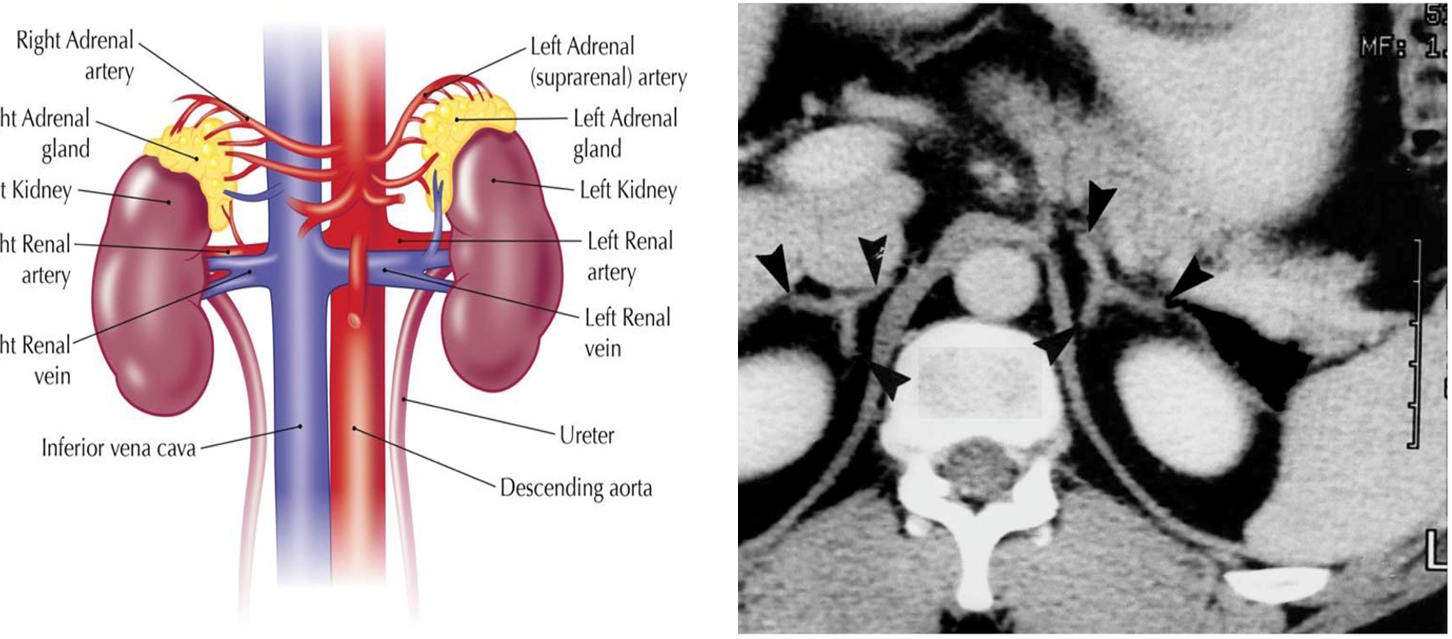

What do the adrenal glands look like on imaging? What is its blood supply?

On imaging, adrenal glands appear like a wish-bone shaped organ that sits anterior and medially to the kidneys

1) These adrenal glands are supplied from three different sources

→ Phrenic

→ Aorta

→ Renal

2) These glands are then drained by the adrenal veins which have different drainages depending on which side it is on:

→ Right adrenal vein drains into the inferior vena cava

→ Left adrenal vein drains into the renal vein